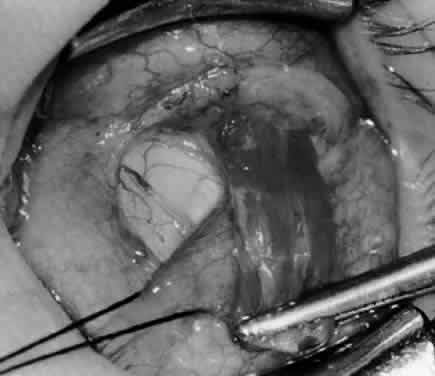

Fig. 5. The Stevens hook is placed adjacent to the posterior edge of the inferior oblique muscle and rotated as the inferior oblique muscle is drawn into the operative field. A forceps is used to retract the redundant Tenon's capsule, encapsulated fat, and intermuscular septum as the muscle is drawn further into the operative field with the Stevens muscle hook.

Fig. 6. The Westcott scissor is used to open the intermuscular septum along the posterior border of the inferior oblique muscle. Care is taken to cut adjacent to the tip of the Stevens muscle hook. This incision is important because it helps to avoid damaging the Tenon's capsule and releasing fat, which leads to the adherence syndrome and postoperative hypotropia.

Fig. 7. A Westcott scissor is used gently to open a space beneath the elevated inferior oblique muscle and allow placement of a Green muscle hook.

Fig. 8. The Green muscle hook is placed beneath the belly of the inferior oblique muscle, and the eye is retracted nasally.

Fig. 9. A Westcott scissor is used to dissect the intermuscular septum and expose the insertion of the inferior oblique muscle.

Fig. 10. The inferior oblique muscle is placed on the Green muscle hook. The exposed insertion is ready for myotomy, myectomy, disinsertion, placement of sutures for recession, or removal for the extirpation procedure.